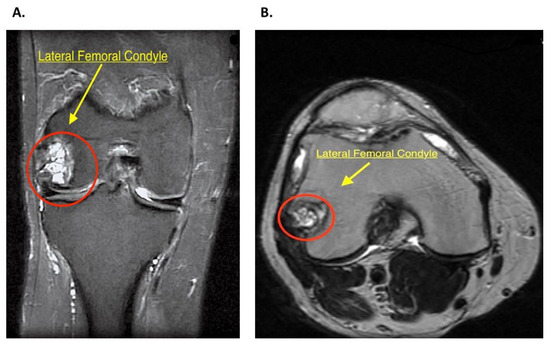

2.2. History and Diagnosis

2.3. Patient Setting